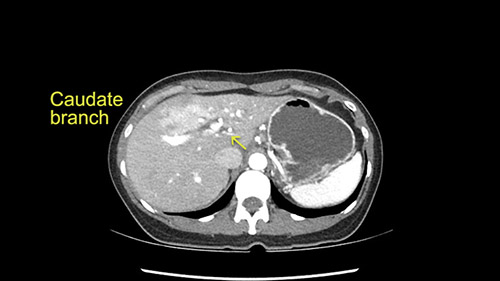

Caudate branch of left portal vein

My plan would be to leave the caudate lobe intact. You usually have to divide the caudate branches. I can see one of the caudate branches here coming off the left portal vein. You usually have to take that to get adequate length although you might be able to divide the portal vein past that left caudate branch.